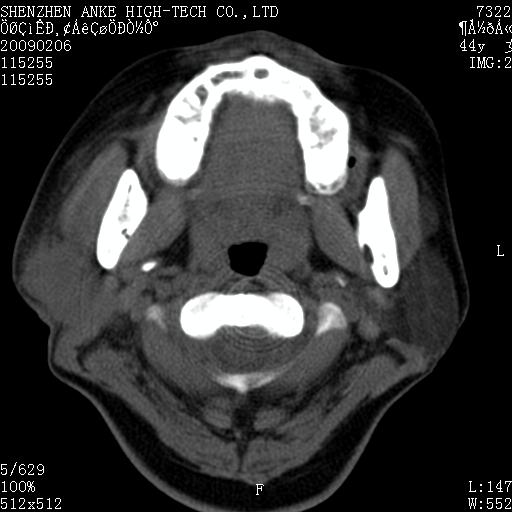

标题: CT17977:女,44岁,右侧颌部包块1年,右侧面瘫2月。 [打印本页]

患者:女,44岁,右侧颌部包块1年,右侧面瘫2月。

考虑右侧腮腺混合瘤可能性大

考虑右侧腮腺混合瘤。

考虑右侧腮腺混合瘤。年轮样伪影考虑机器问题!

右侧腮腺混合瘤可能性大

考虑右侧腮腺混合瘤;不排除腮腺癌。

右侧腮腺肿瘤,良恶性难定。

右侧腮腺混合瘤。机器没有调试好。